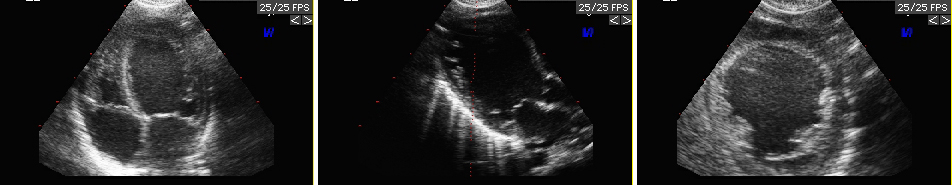

This page is intended to give additional information about dolichol kinase deficiency. The corresponding paper has been published in the March 2007 issue of the American Journal of Human Genetics. Movie of one of the patients for download (13 Mb)(The movie is encoded by DivX and optimized for viewing with Microsoft Windows based computers. Please note that it will only play if you have the DIvX codec installed on your computer. With the DivX codec installed, it should play fine on Macintosh computers as well. You will get the free codec for your computer here.)The patient is shown at 6 months of age. The movie shows the profound muscular hypotonia.A movie of the severe dilative cardiomyopathy will be available on this page soon.For further information please contact marquat@uni-muenster.de